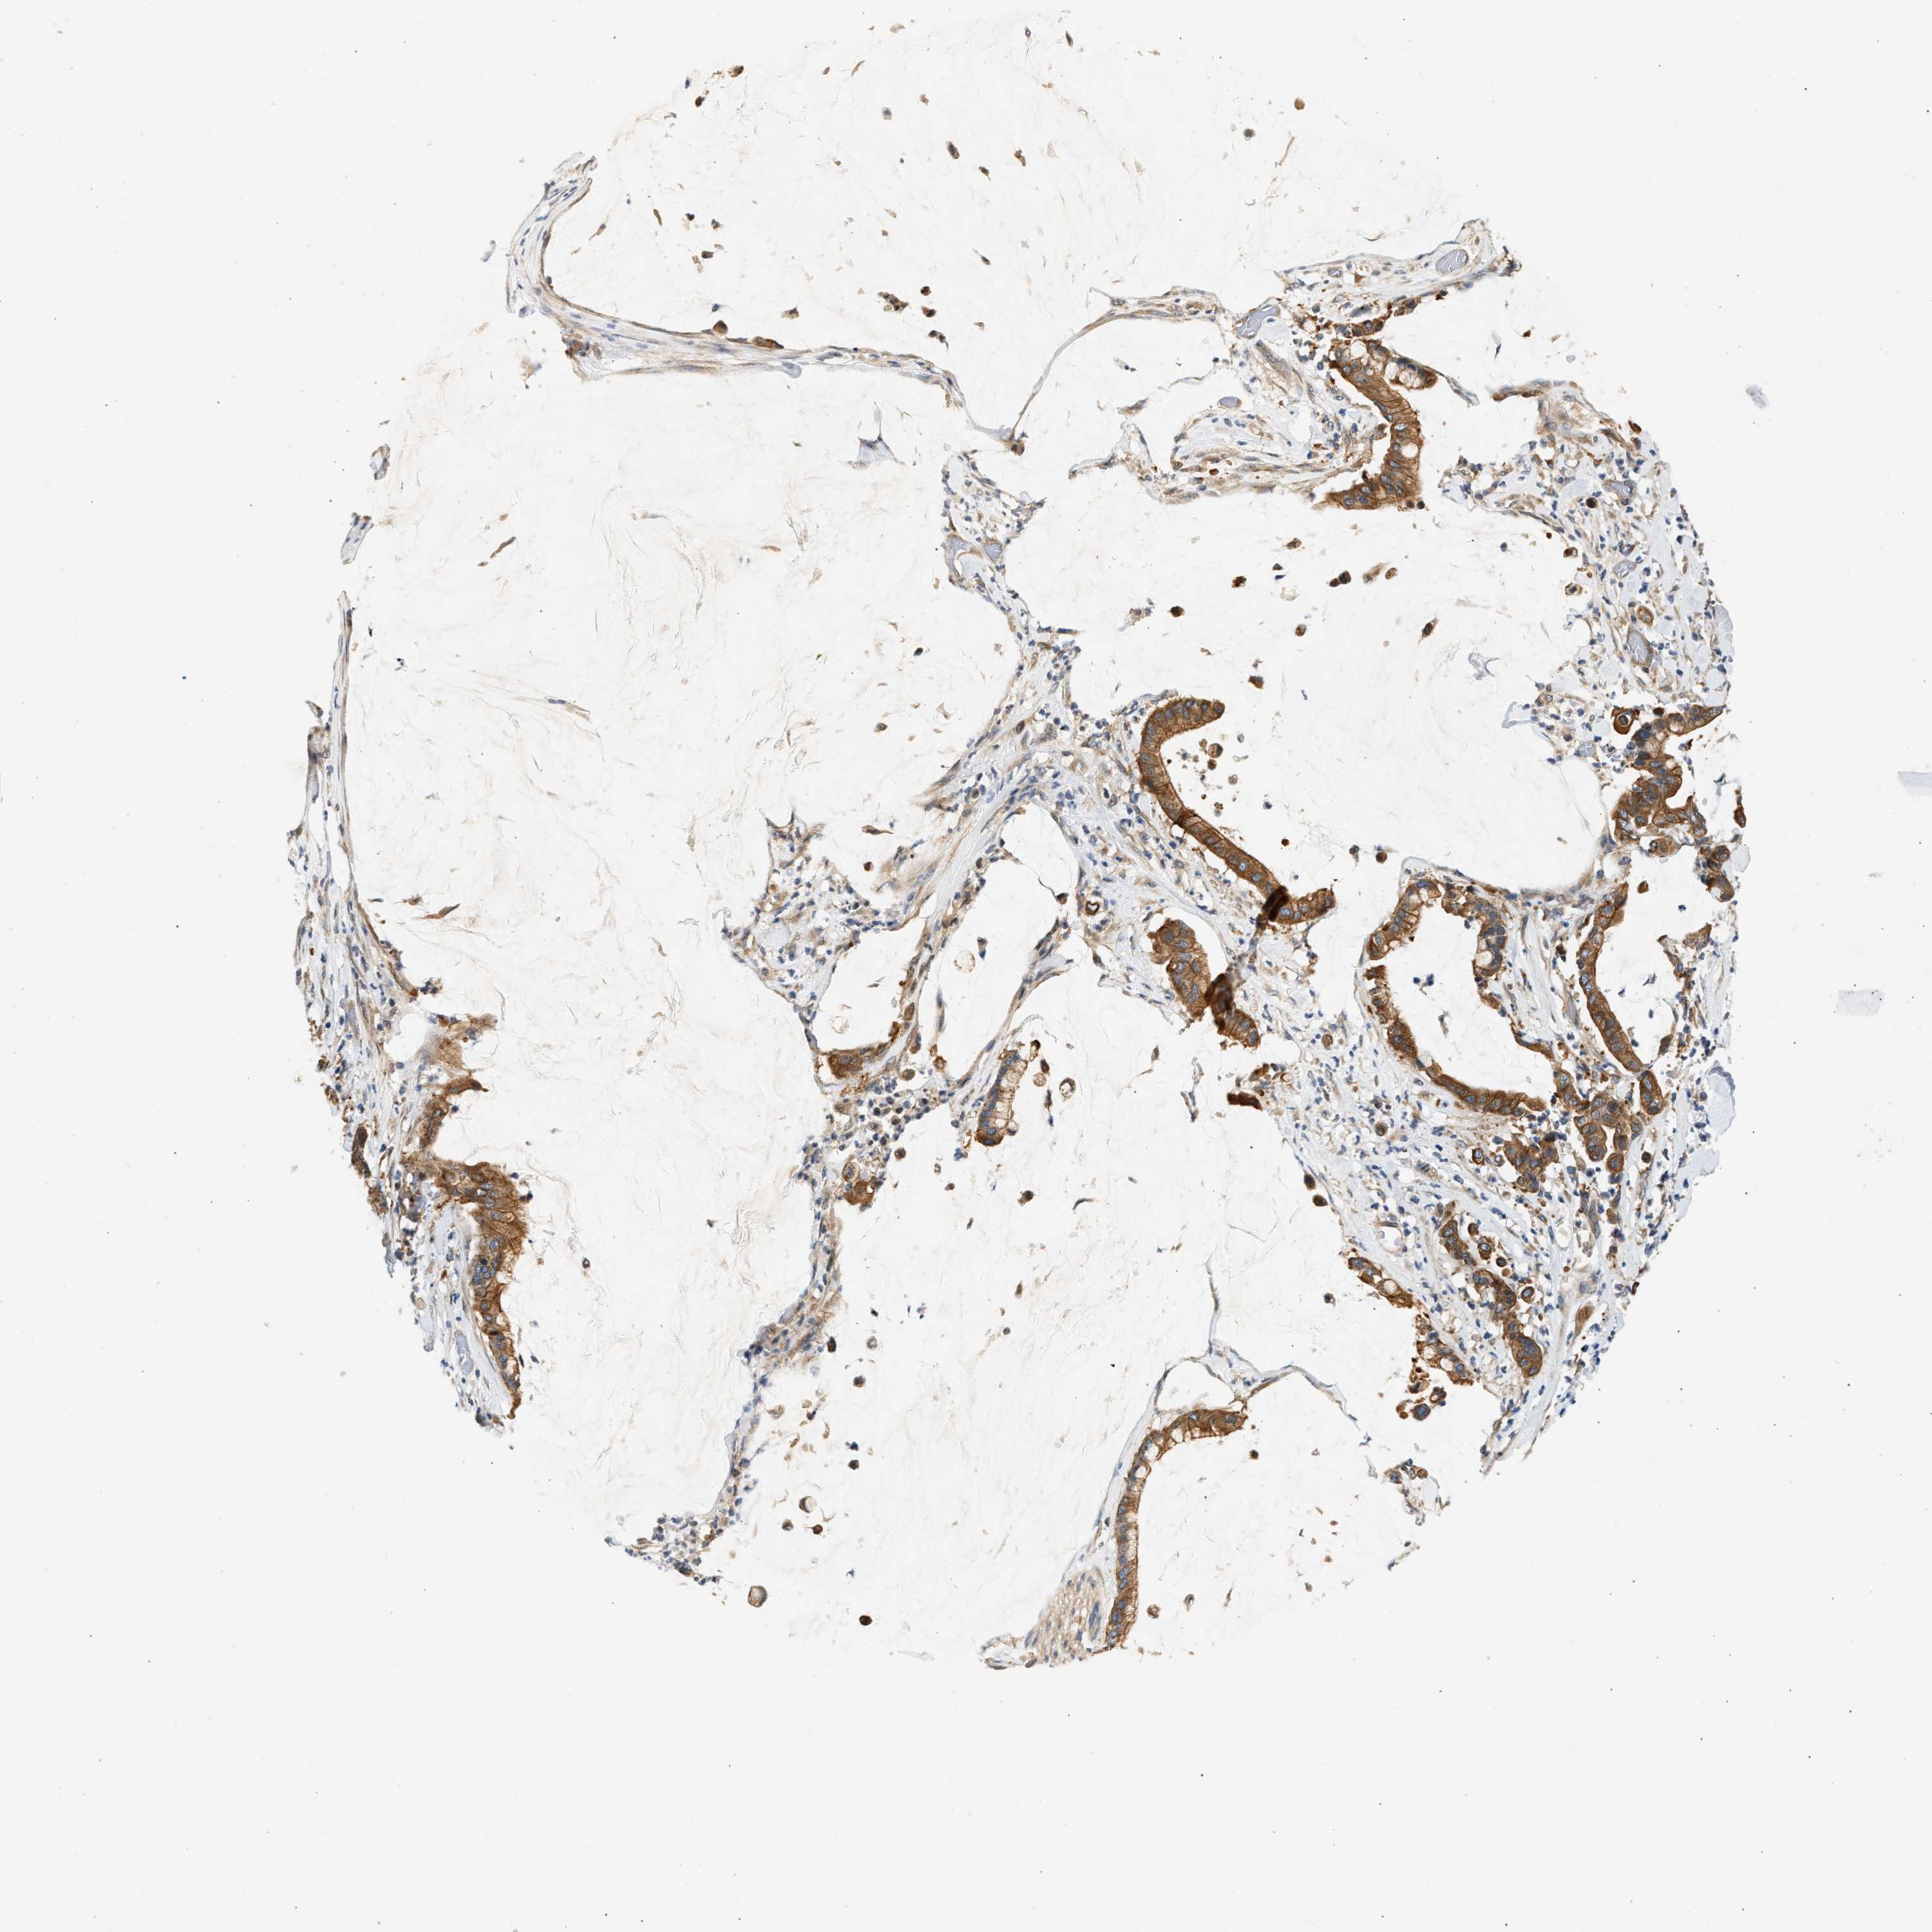

PANCREATIC CANCER - Protein expressioni

A mouse-over function shows sample information and annotation data. Click on an image to view it in a full screen mode. Samples can be filtered based on level of antibody staining by selecting one or several of the following categories: high, medium, low and not detected. The assay and annotation is described here.

Note that samples used for immunohistochemistry by the Human Protein Atlas do not correspond to samples in the TCGA dataset.

Antibody stainingi

Antibody staining in the annotated cell types in the current human tissue is reported as not detected, low, medium, or high, based on conventional immunohistochemistry profiling in selected tissues. This score is based on the combination of the staining intensity and fraction of stained cells.

Each image is clickable and will lead to virtual microscopy that enables deeper exploration of all samples and also displays staining intensity scores, fraction scores and subcellular localization as well as patient and tissue information for each sample.

Antibody HPA019340

Antibody HPA019347

Staining

High

Medium

Low

Not detected

Intensity

Strong

Moderate

Weak

Negative

Quantity

>75%

75%-25%

<25%

None

Location

Nuclear

Cytoplasmic/membranous

Cytoplasmic/membranous,nuclear

Adenocarcinoma, NOS